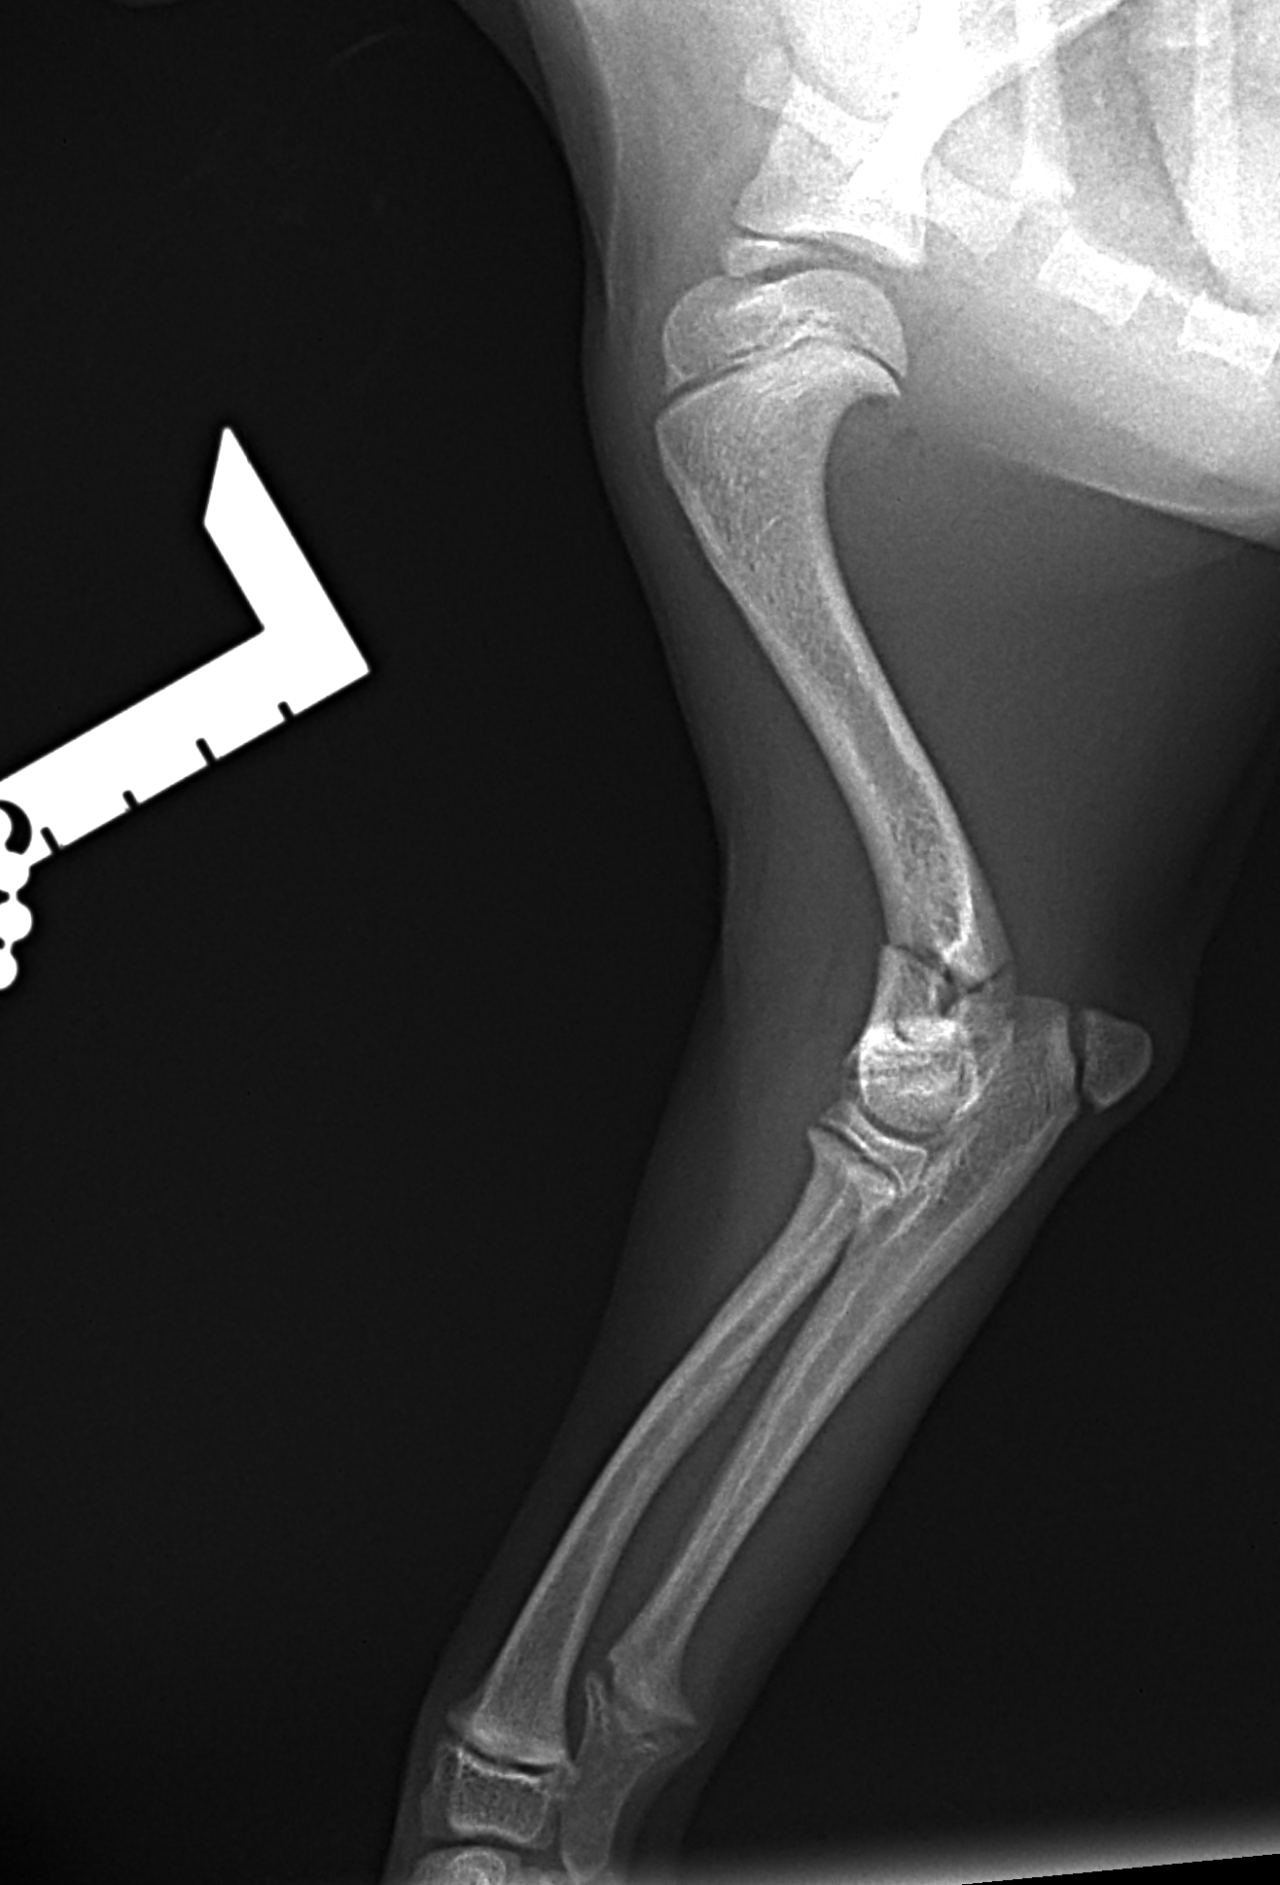

超小型犬に対する上腕骨遠位Y字骨折

4ヶ月齢 体重1.2kgの極小犬に発生した上腕骨遠位Y字骨折に対し、2.4mmキャニュレイティッド・ヘッドレス・コンプレッションスクリューを用いた整復固定を実施しました。(Rita LeiCOM cannulated compression screw) 患者さんの骨格は非常に小さく、最小侵襲かつ関節面の解剖学的整復を重視し、ガイドワイヤーを用いた正確なスクリュー挿入により圧迫固定を行いました。術後は良好なアライメントを維持し、関節機能の温存が期待される結果となっています。極小犬の関節内骨折においては、インプラント選択と精度の高い操作が予後を大きく左右することを改めて実感する症例でした。